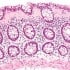

How Digestion Works & The Impact of Gluten on the Digestive System